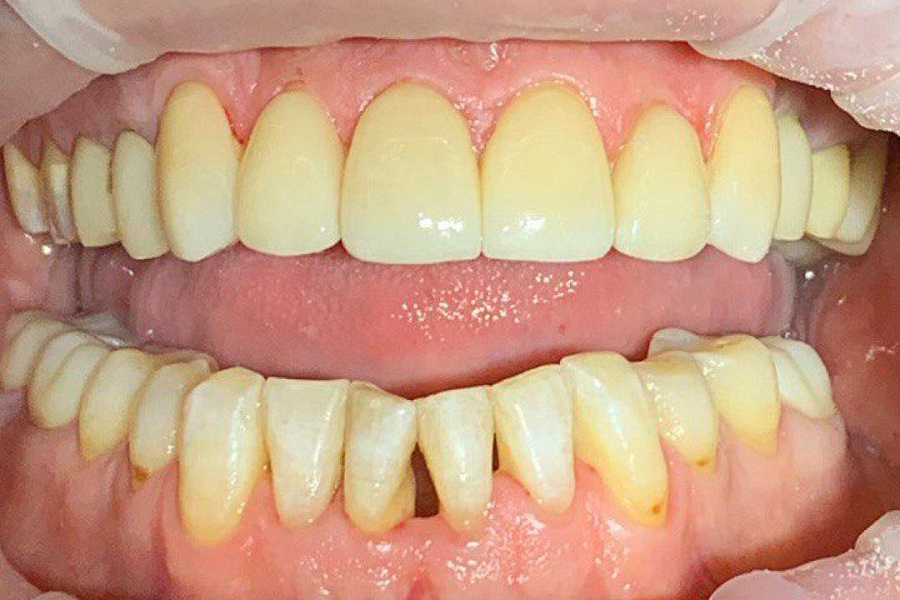

Наш постоянный клиент, который настаивал только на лечении кариеса. Несмотря на ряд проблем: стираемость зубов, перекрестный прикус, который и вызывал увеличение стираемости, пациент не хотел делать комплексную работу.

В итоге из-за неправильного прикуса стираемость зубов прогрессировала и нам удалось убедить пациента заняться данной проблемой серьезно.

1. Восстановлена правильная позиция зубов с помощью ортодонтического лечения под наблюдением гнатолога, но в связи с высокой стираемостью этого было недостаточно.2. Была проведена ортопедическая реабилитация ортопедическими конструкциями с восстановлением высоты нижней трети лица и формы стертых зубов.

В результате мы получили сохранность ситуации , которая не ухудшается дальше. Лицо стало более молодым и подтянутым. Пациент перестал скрипеть зубами и стирать свои собственные зубы.